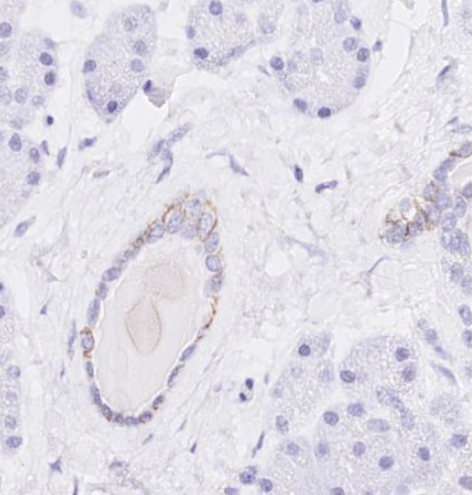

Staining pattern: Membranous staining |

A moderate to strong, membranous staining reaction of virtually all columnar epithelial cells in appendix. No staining in smooth muscle cells. |

A moderate membranous staining reaction in scattered columnar epithelial cells in pancreas |

No staining reaction in liver |